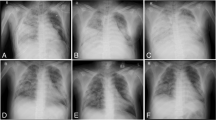

On the third day post-trauma, the patient developed ACS (intraabdominal pressure >30 mm H2O, as measured using a pressure transducer in the urinary bladder, which had been filled with 100 mL of NaCl). Renal function was impaired (oliguric), and lung compliance deteriorated extensively and rapidly within an hour (tidal volume less than 50 mL on ventilator settings with PEEP 15 and inspiratory pressure of 35 cm H2O). Exploratory laparotomy was performed at the patient’s bedside. The renal function had improved, but lung compliance had not. Postoperatively, the ventilator was disconnected, and the endotracheal tube was left blocked in the trachea, with a T-piece placed at the end of the tube. Thus, gas exchange was achieved through VV ECMO alone. During the next 48 h, the patient’s sedation was weaned and respiratory effort (thorax movement) was observed. The spontaneous breaths were sporadic, occurring at a rate less than 10 per minute, and very shallow. Percutaneous dilatational tracheotomy was performed. Subsequently, assisted ventilation with very low tidal volumes (20–30 mL) was initiated. No atelectasis was present. The patient’s lung compliance increased to 300 mL over the following 3 days. The patient was weaned from VV ECMO and mechanical ventilation on days 9 and 13, respectively, after the trauma (Fig. 1). He was discharged from the ICU after 16 days and from the hospital after 49 days. His recovery and outcome after 12 months follow-up revealed no neurological disability.